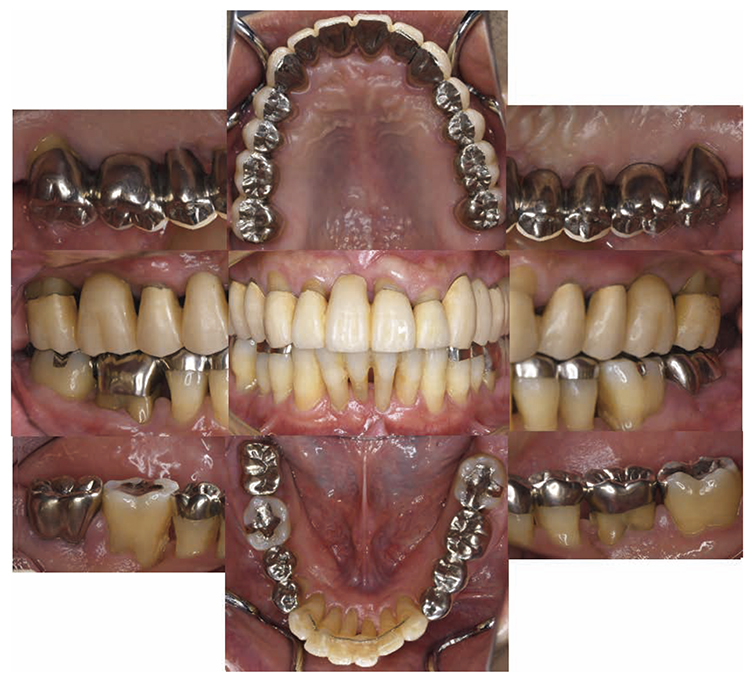

2) Intraoral findings

(1) Macroscopic findings

No obvious redness and swelling were present in the marginal gingiva across the full jaw; some blood congestion was however observed. The gingival shape of the anterior teeth in the mandible and maxilla was that of a thick shelf. Significant gingival recession was observed on the mandibular anterior teeth and the buckle side of the left and right maxillary first molar. The dental arch on the maxilla and mandible had a parabolic shape. Teeth separation was however observed between the maxillary central incisors, maxillary right central incisor and lateral incisor, maxillary right canine and first premolar, maxillary left canine and first premolar, and crowding was observed in the mandibular central incisors (Fig.1a).

(2) Examination of periodontal tissue

At the time of first visit, the average PD (Probing Depth) on the full jaw was 4.5mm,maximum PD was 10.0mm, 43.5% had PD of 3mm or less,38.7% for 4-6mm,17.9% for 7mm or above. The average BOP (Bleeding on Probing) on the full jaw was 42.3%,teeth mobility on 17,22,23,32,33,41,46 was grade 1,grade 2 on 11,12,21,and grade 3 on 16,24,26,31 (Miller classification). Additionally, grade 1 on 36,16(mesial, distal),26 (mesial, distal) and 36,grade 2 furcation involvement (Lindhe & Nyman classification) was observed on 47. The plaque score at the first visit (O’Leary’s Plaque Control Record:PCR value) was 83.9%, which indicated poor oral hygiene status (Fig.1b).

Fig 1a

(Fig.1a) Intraoral photo taken during first visit (June 2007)

Fig 1b

(Fig.1b) Results of periodontal tissue examination during first visit (June 2007)